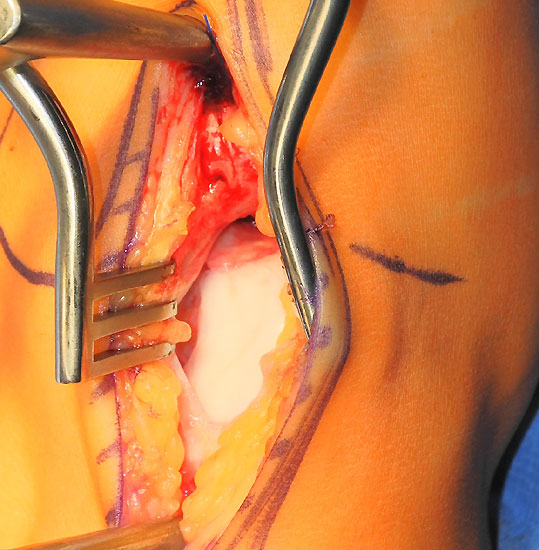

Operationstechnik (Fotos und Video)

Je nach Lage des Knorpeldefektes sind verschiedene Zugänge möglich. Ziel ist einen guten Zugang zum Defekt zu erreichen bei gleichzeitiger Vermeidung einer Innenknöchelosteotomie.

Die Darstellung der weiteren Operationstechnik erfolgt am Beispiel eines medialen Zugangs bei einer Osteochondrosis dissceans mit subchondraler Zyte der medialen Talusschulter (siehe MRT Abbildung 1).